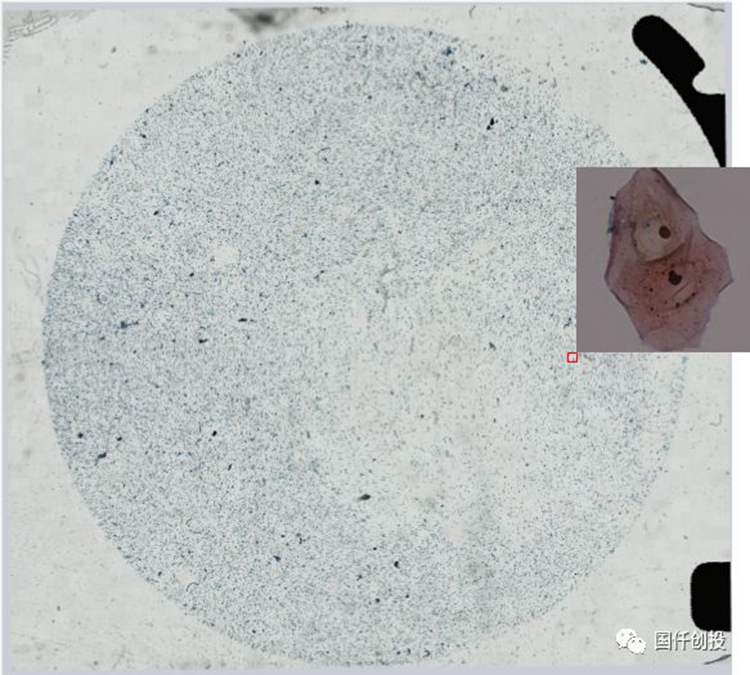

蘇州睿仟醫(yī)療科技有限公司

完成工程樣機(jī)的開發(fā)并實(shí)現(xiàn)了高速、高質(zhì)量的圖像掃描

6月

完成病理圖像無縫拼接軟件的開發(fā)

7月

完成病理標(biāo)注、虛擬全景病理圖像預(yù)覽軟件系統(tǒng)的開發(fā)

完成搭建包含實(shí)現(xiàn)數(shù)據(jù)、訓(xùn)練、可視化等標(biāo)準(zhǔn)工具的細(xì)胞病理判讀AI流程框架